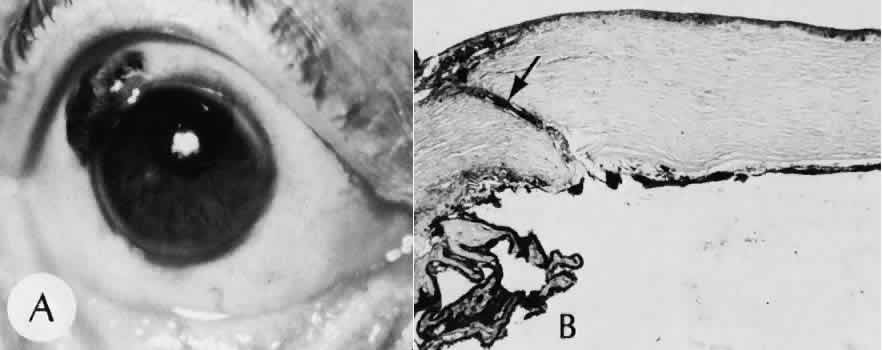

Fig. 33. A case of iris prolapse through a limbal wound. A. A large black mass has appeared at the limbus of a patient with a history of cataract extraction. There may or may not be a history of trauma or Valsalva maneuver. The differential diagnosis at first glance would certainly include primary conjunctival malignant melanoma or extraocular extension of a primary uveal malignant melanoma. A major differential observation from iris prolapse is the character and degree of alteration of the iris tissue remaining within the eye. B. By histologic section no cellular mass is present either in the episcleral or uveal tissue. The remaining iris is stretched and adherent to the posterior corneal surface. (Hematoxylin-eosin stain; × 40.)